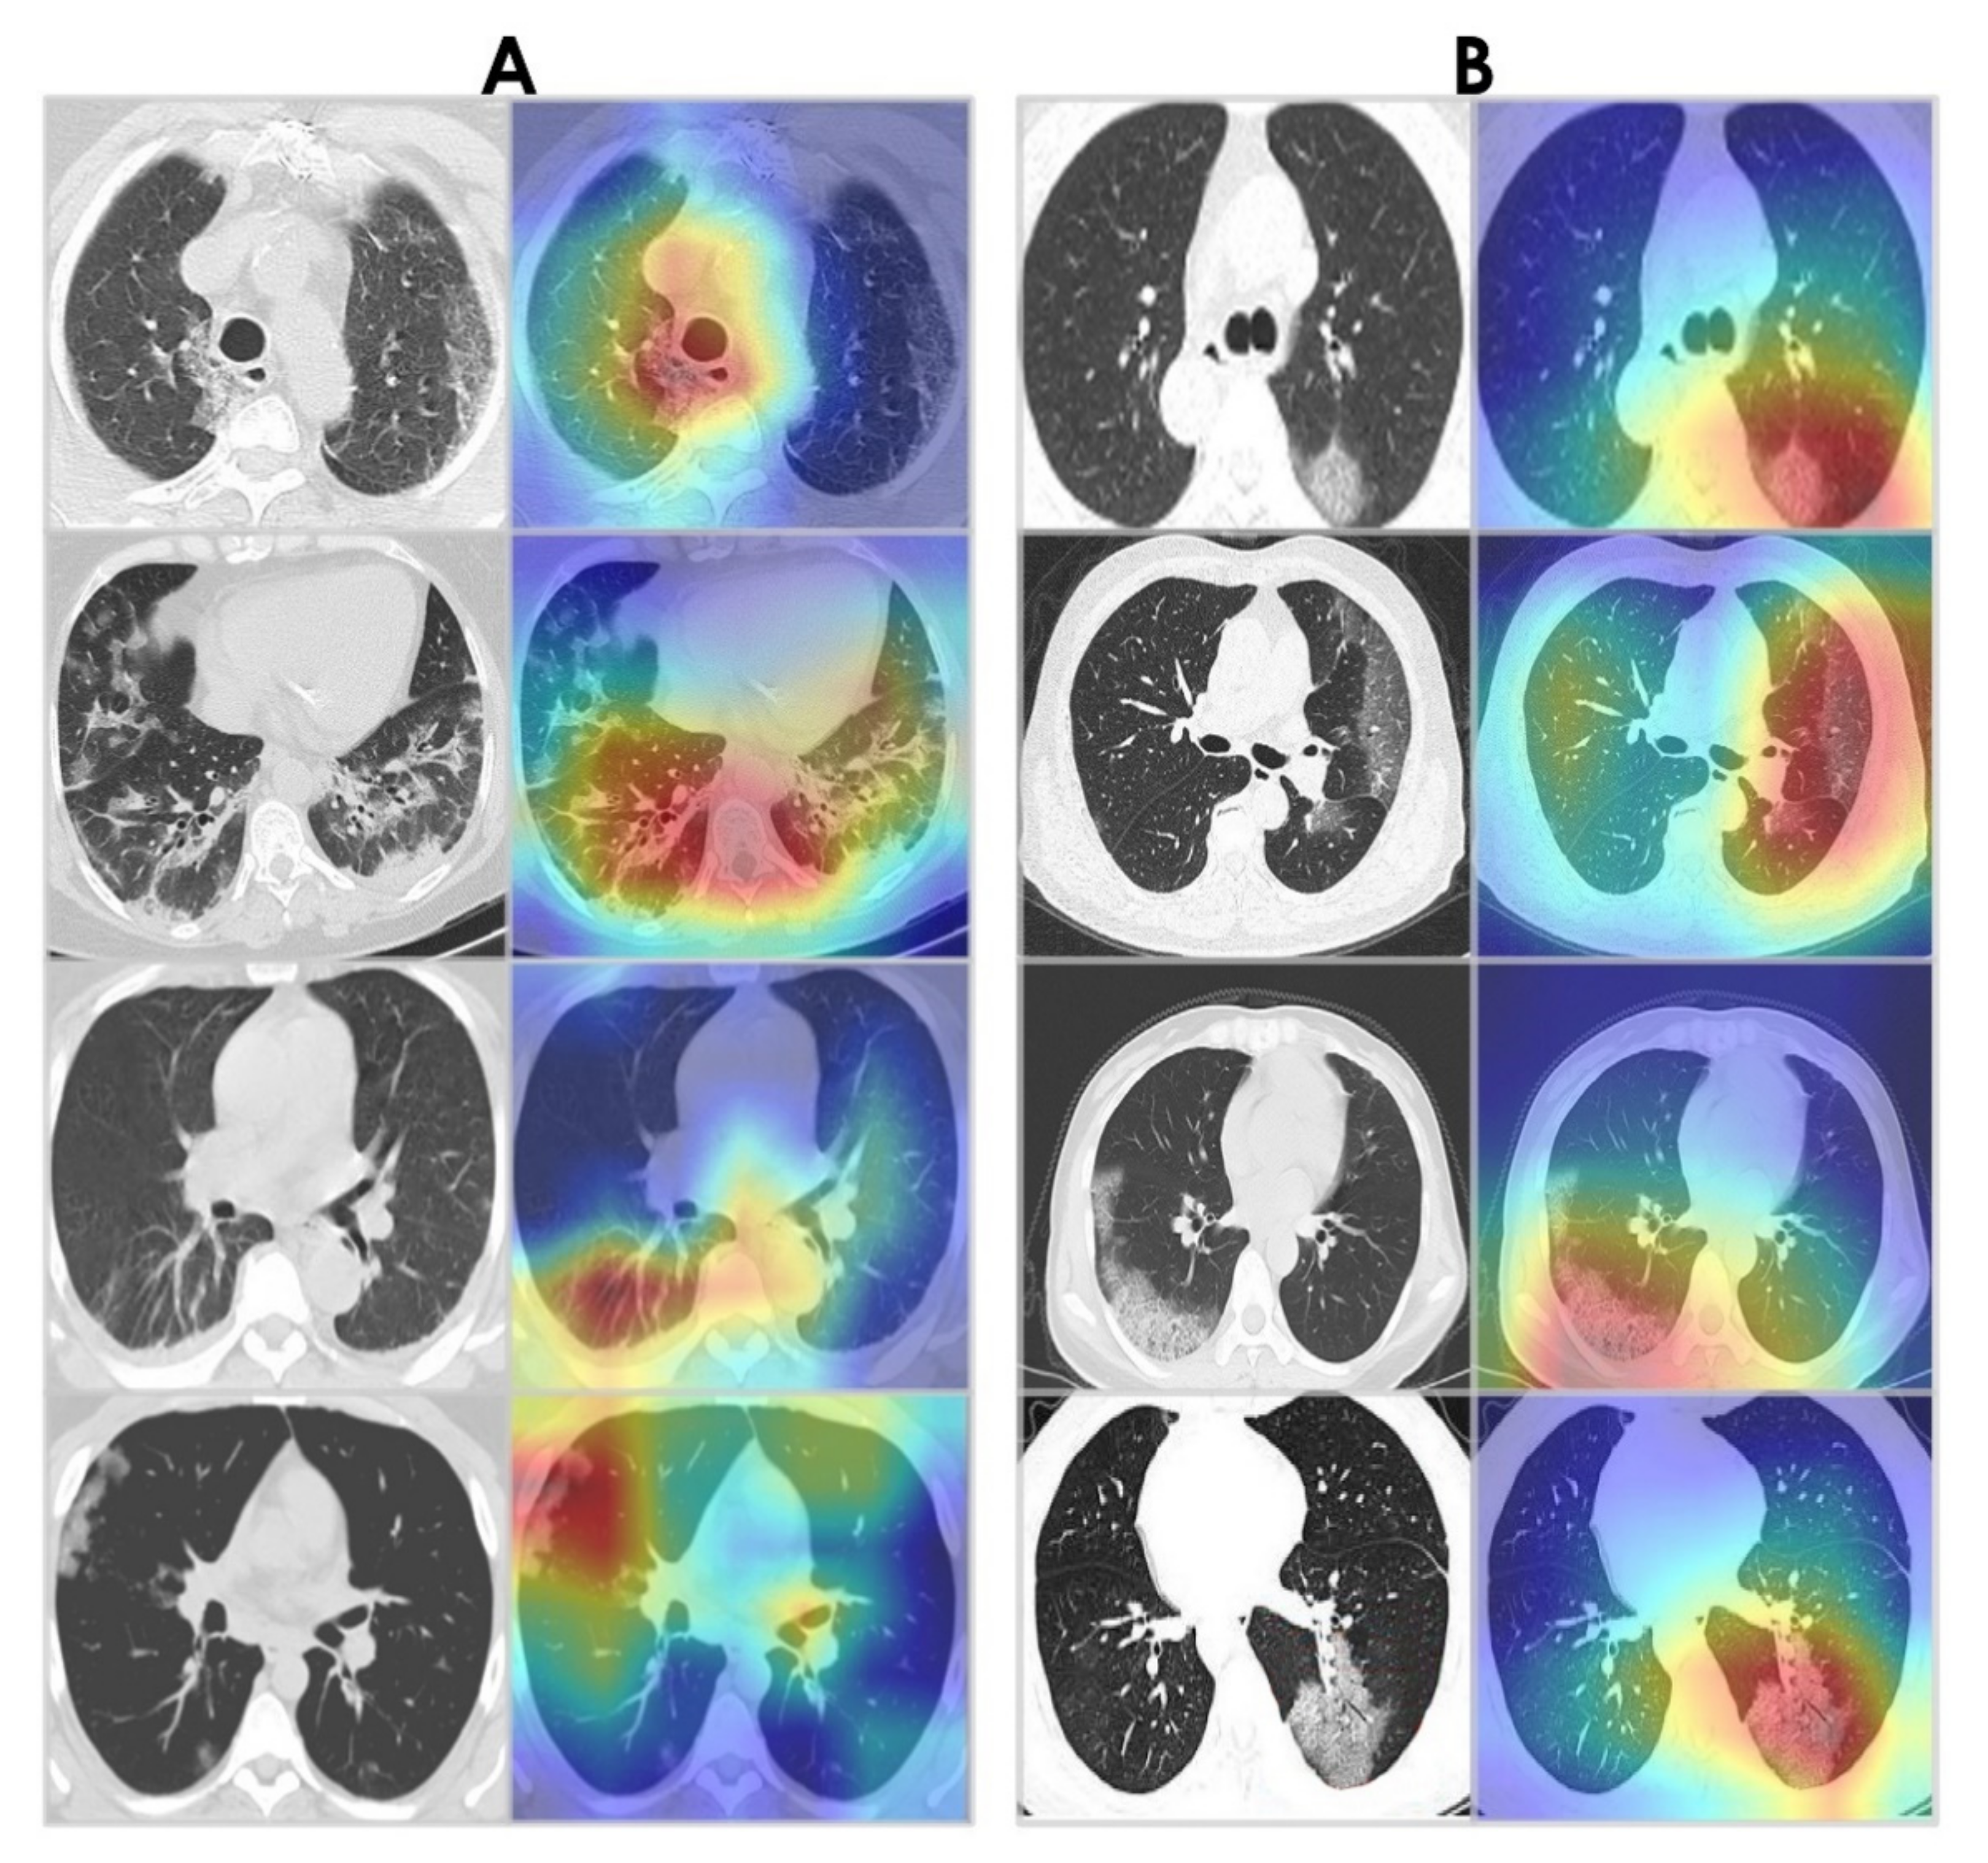

4.5. Grad-CAM Visualizations

Grad-CAM algorithm [67] was used to examine the behavior of the WAE network by visualizing the areas of infection in our chest CT images. This provides insight into what the network has learned and what part of its input contributed to detecting COVID-19. Grad-CAM visualizations for WAE are shown in Figure 19. Note that the WAE’s area of interest at the time of prediction is represented by the red and green visuals. It is noticed that the activations maps are focused on the lungs. Interestingly, in the majority of cases, WAE was able to localize the disease region based on relevant features from the chest CT images for both datasets.

Figure 19. Grad-CAM visualizations. (A) Sample CT images from the SARS-CoV-2 CT-scan dataset [42]. (B) Sample CT images from the COVID-CT dataset [22].